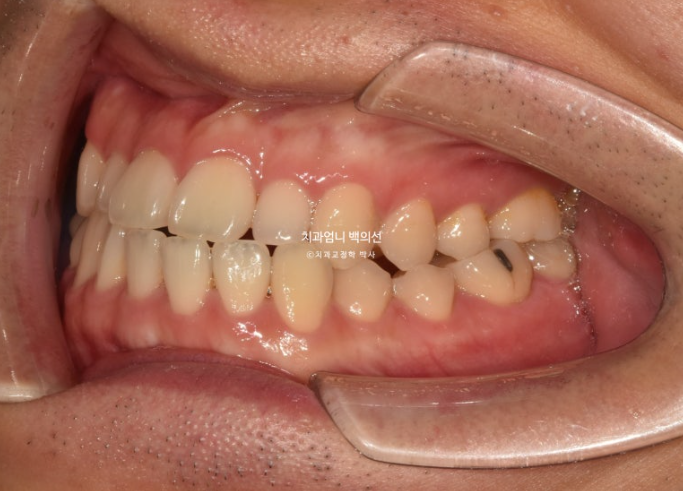

어금니 교합은 3급입니다.

치료계획을 크게 보면 아래 전치치아를 뒤로 밀면서 어금니 교합을 1급으로 맞추고 위 앞니가 아래 앞니를 덮도록 하는 것이 메인입니다.

이를 위해 아래 왼쪽 사랑니는 발치를 하고 작은어금니 하나가 없는 반대쪽은 사랑니 발치를 하지 않습니다.

사랑니 공간으로 치아들을 밀 때 불리하긴 하지만 좌우 치아 갯수 밸런스를 맞추기 위해서입니다.

치료 시작 10개월차 모습입니다. 교정용 나사인 미니스크류를 아래쪽에 심고 사랑니 공간으로 밀어냅니다.

24.11